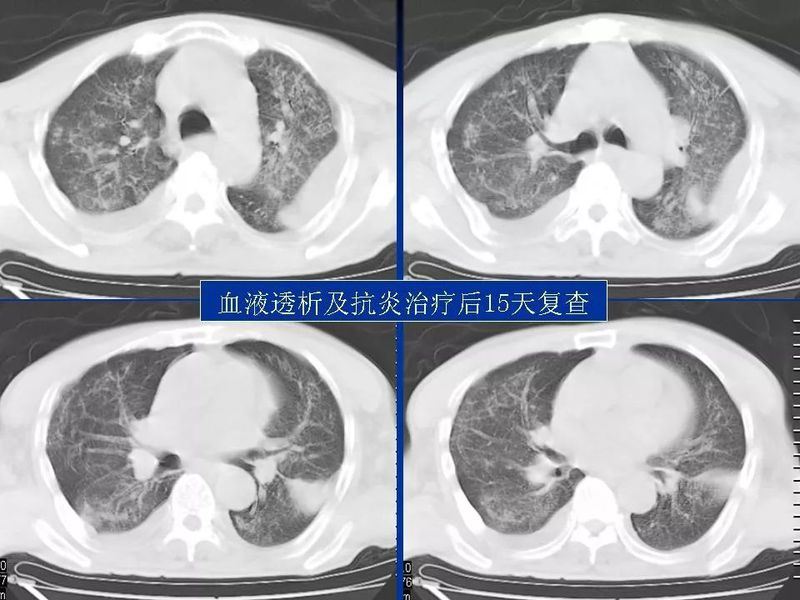

主任提醒:这个病很容易误诊为肺炎!